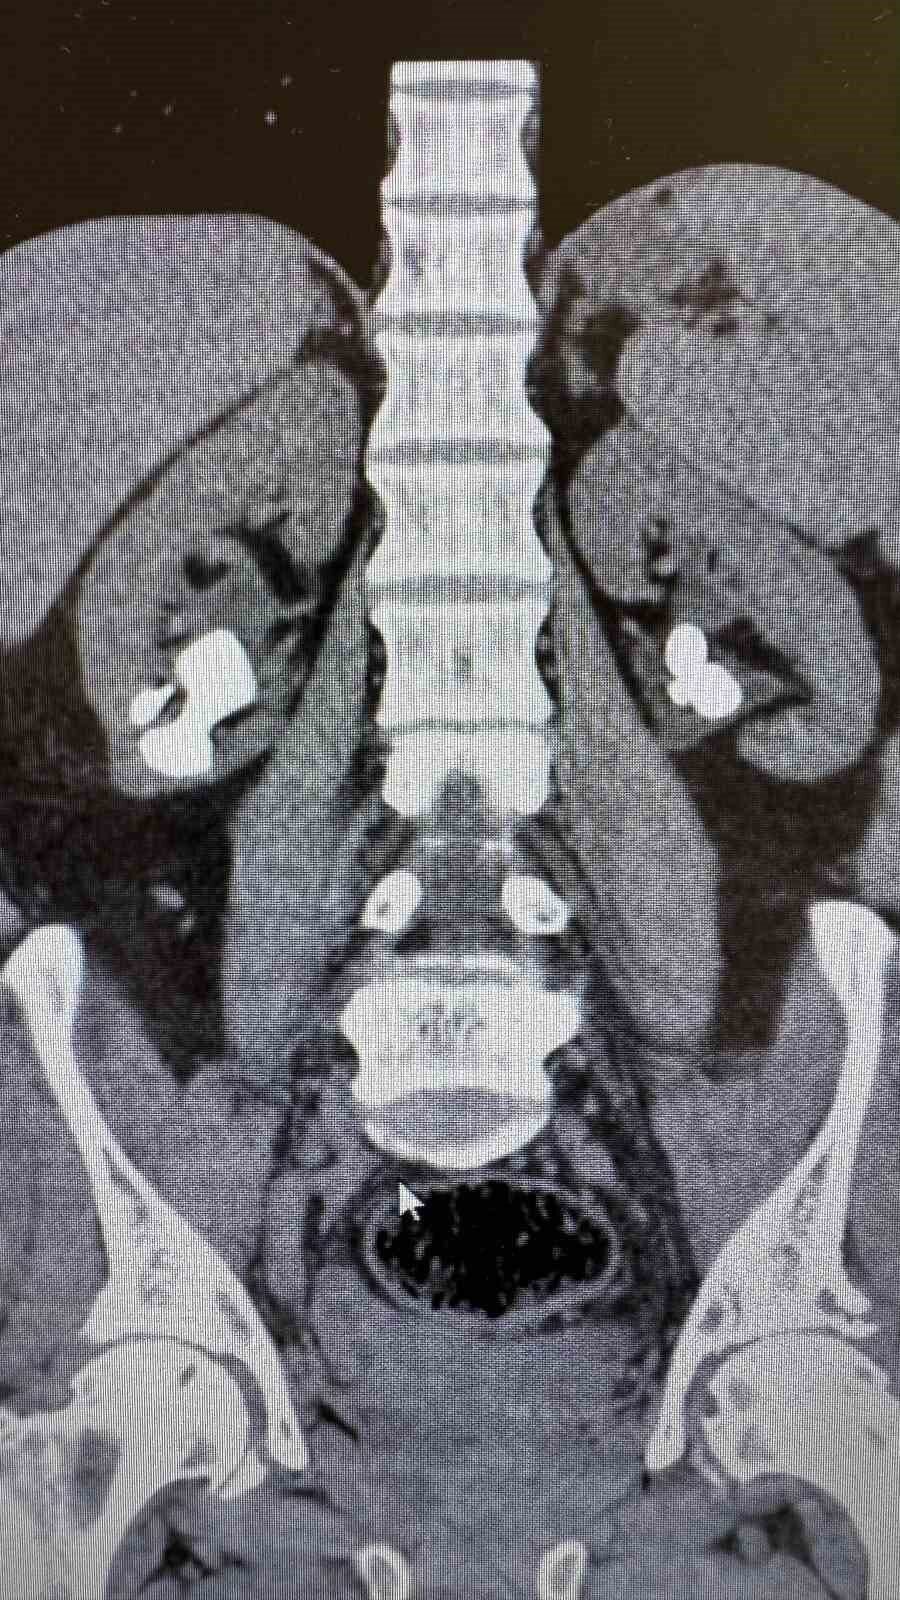

Antalya Gazipaşa Devlet Hastanesi’nde gerçekleştirilen iki başarılı operasyonla 62 yaşındaki hasta böbrek taşlarından tamamen kurtuldu.

Üroloji Uzmanı Op. Dr. İlker Fatih Şahiner ve ekibince kapalı yöntemle (PNL) yapılan ameliyatlarda hastanın her iki böbreğindeki tekrarlayan sistin taşları temizlendi. Hastanın daha önce 10’un üzerinde böbrek taşı ameliyatı geçirdiği öğrenildi. Mayıs ayında yapılan ilk operasyonla sol böbrekteki taşlar alınırken, geçtiğimiz salı günü gerçekleştirilen ikinci operasyonla sağ böbrekteki taşlar da temizlendi.

Operasyonları gerçekleştiren Üroloji Uzmanı Op. Dr. İlker Fatih Şahiner, “Hastamızın her iki böbreğinde de tekrarlayan sistin taşları mevcuttu. Mayıs ayında sol böbreğine PNL yaparak taşsızlık sağlamıştık. Dün de sağ böbreğine PNL ameliyatını yaparak taşsızlık sağladık. Hastamızın genel durumu iyi, tedavisi servisimizde devam ediyor” dedi.

Başarılı operasyonların ardından hastanın yıllardır süren böbrek taşı sorunundan tamamen kurtulduğu bildirildi.